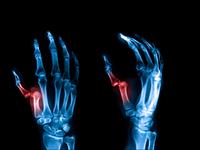

Izmežģījums ir pilnīga kaulu locītavu galu pārvietošanās attiecībā vienai pret otru. Aktīvas kustības kļūst neiespējamas.

Izmežģījies īkšķis